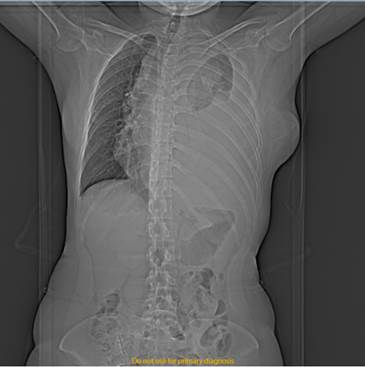

Figura 2:  Radiografía de tórax AP, se observa derrame pleural izquierdo, con presencia de tabicaciones en su interior, volumen aproximado de 2000cc

Imagen tomada de: Caso Clínico Clínica Abendaño.  Loja - Ecuador

El estudio radiológico por medio de una TAC simple mostró tejidos blandos y elementos óseos que integran la pared, sin evidencia de alteraciones. Se visualiza adenomegalias en el nivel IV izquierdo de 27 mm, otras imágenes ganglionares más pequeñas de entre 9mm. Aorta, troncos supra aórticos y arterias pulmonares impresiona de calibre normal. (Fig. 4) Llama la atención masa mediastinal anterior isodensa al músculo, que desplaza las estructuras mediastinales hacia la derecha, mide aproximadamente 19,6 x 12 x 10 cm. Corazón de tamaño y morfología normal. Con ventana de pulmón se observa campo pulmonar izquierdo colapsado, el derecho no se observa zonas de infiltrados ni consolidación. Derrame pleural izquierdo, con presencia de tabicaciones en su interior, volumen aproximado de 2000cc.